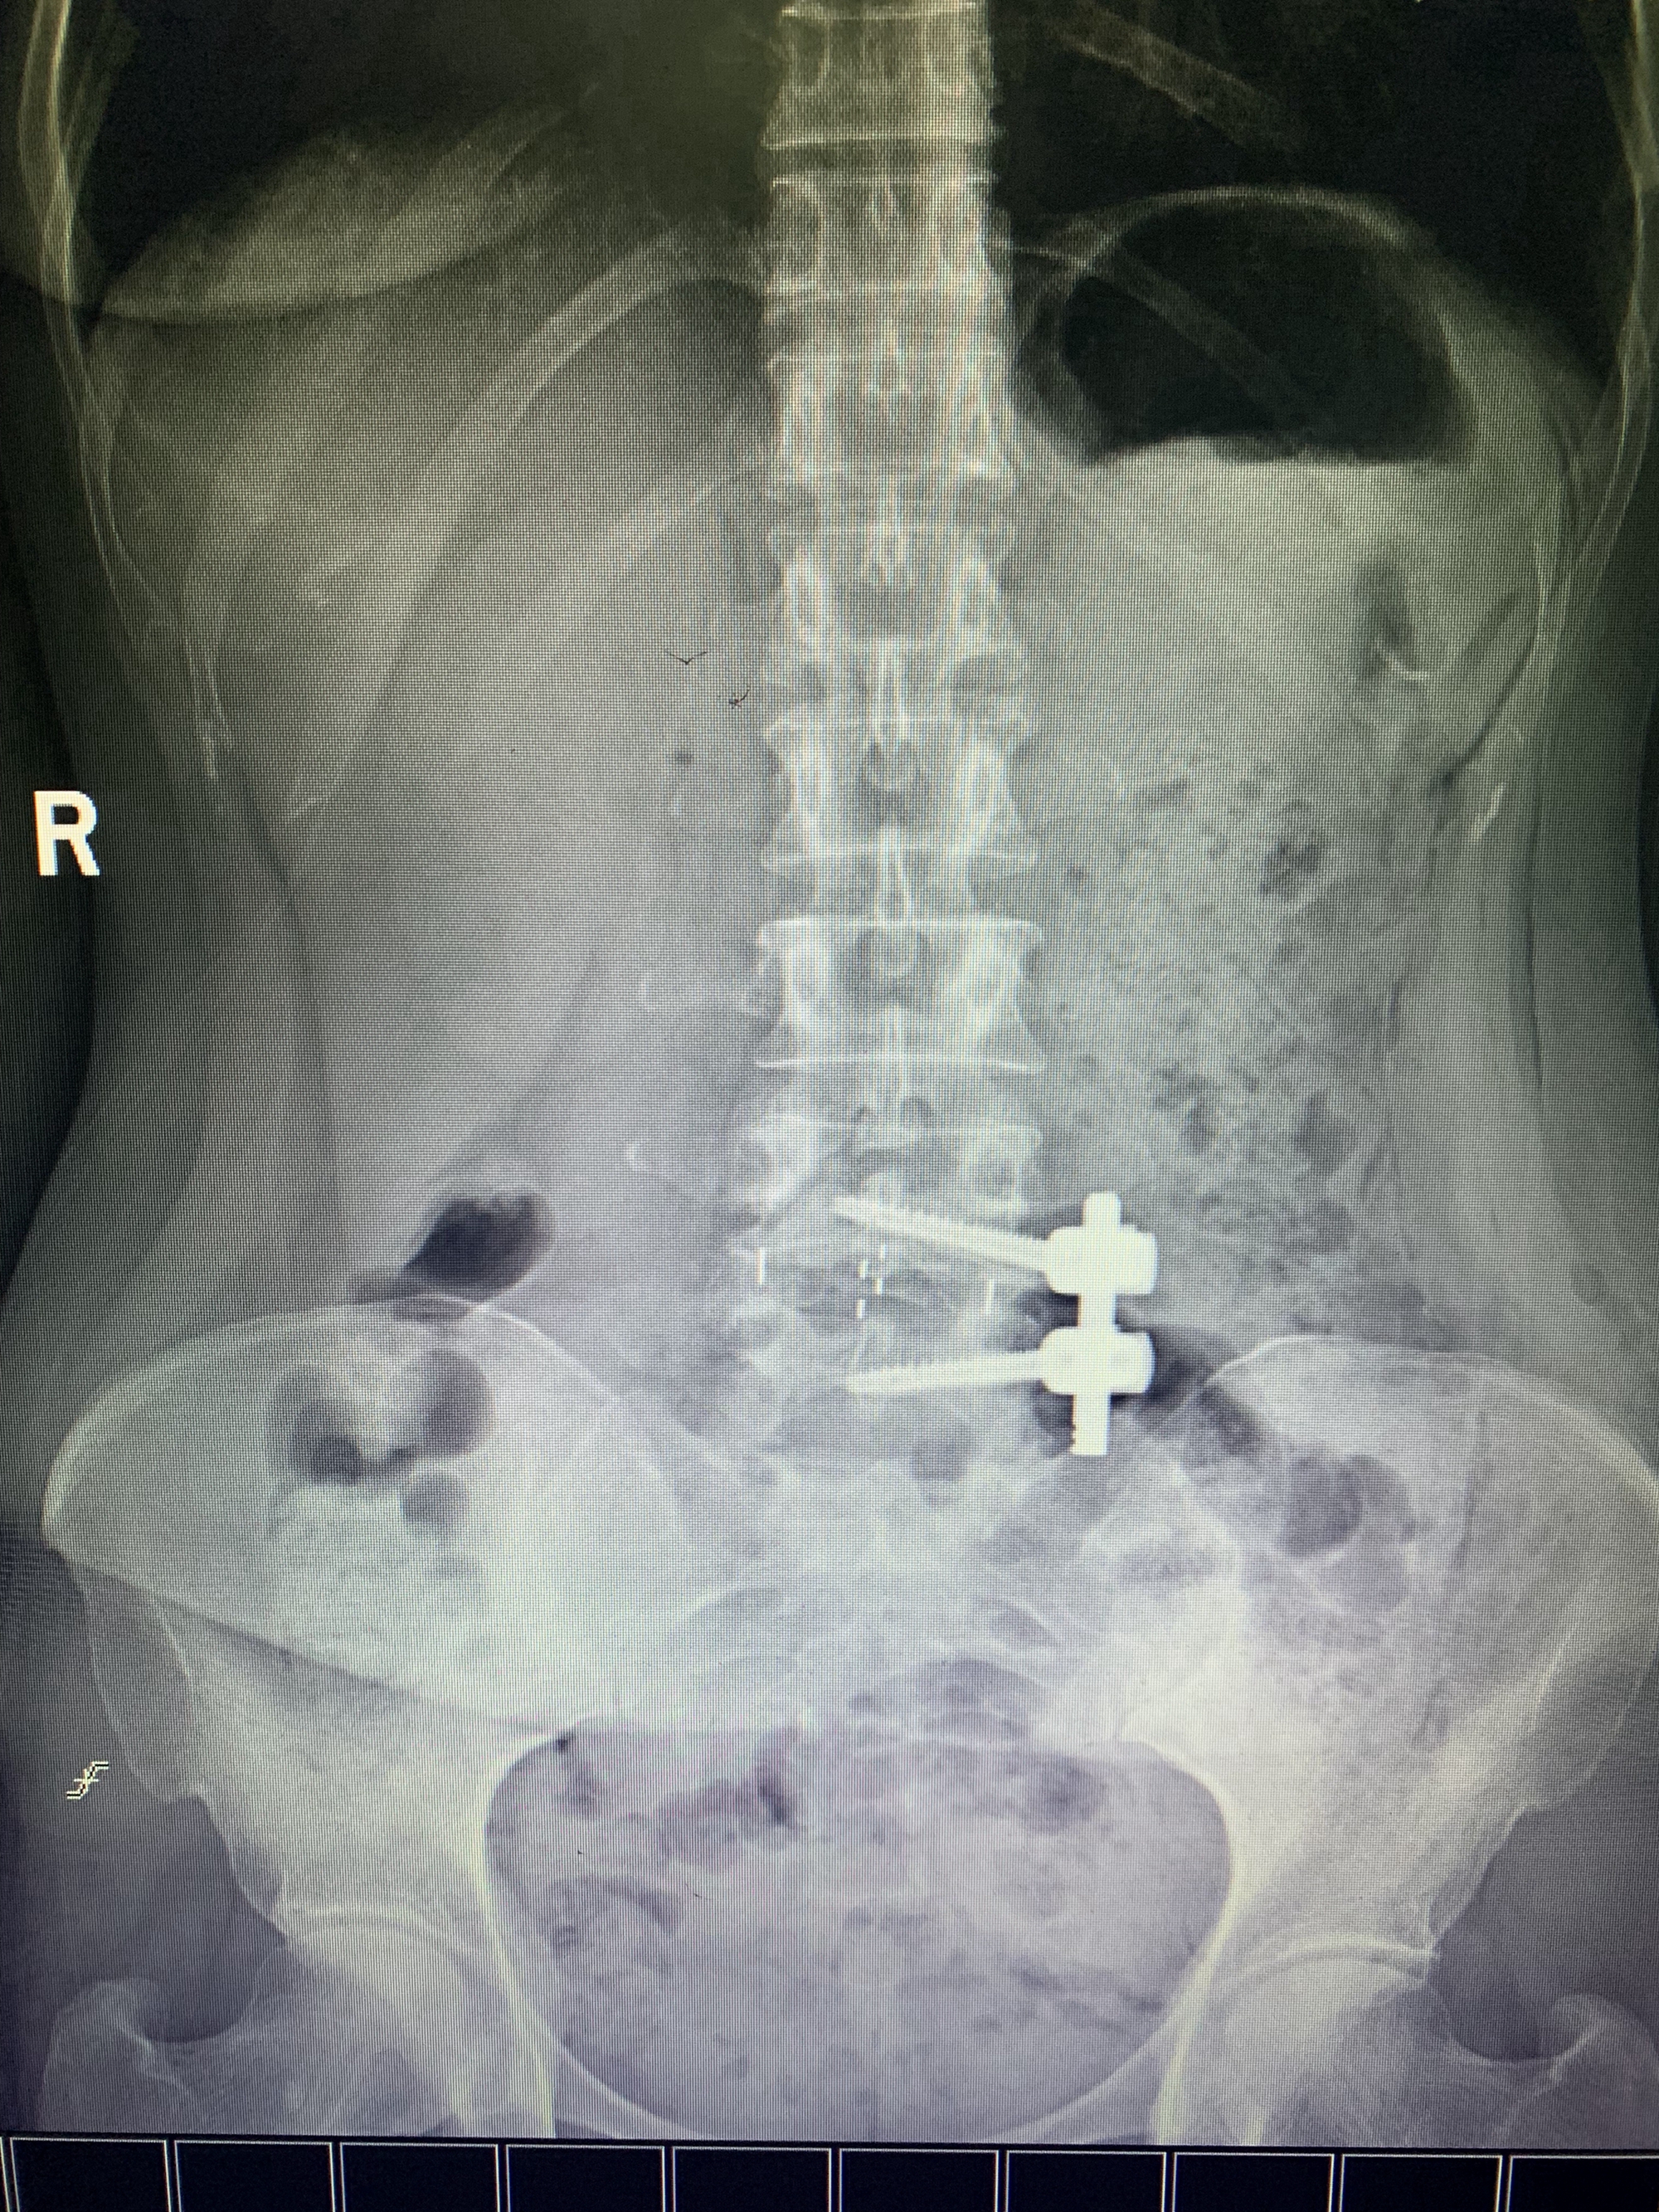

近日,在复旦大学附属中山医院脊柱外科顾宇彤教授的技术指导下,我院骨科戴福全主任医师及其团队协同,顺利完成了我市第一台“经皮椎间孔镜下L4/5椎间盘切开髓核摘除+微创腰椎前斜外侧椎间植骨融合及椎弓根螺钉内固定术”,以下简称腰椎间孔镜+OLIF手术。解决了患者因腰椎滑脱及椎间盘突出压迫神经根而产生的腰腿痛及活动障碍。此类手术的成功开展,标志着我院骨科的脊柱外科微创水平又上一个新的台阶。

患者因反复腰腿痛伴活动受限3年,加重数月,近日无法耐受长时间行走及站立,生活质量低。曾在多家医院诊断为:1、L4/5椎间盘突出症;2、L4椎体前滑脱(Ⅰ度)。为求进一步治疗来我院就诊。入院积极完善相关术前检查,考虑传统腰椎滑脱手术时间长、创伤大、出血多。

经与顾教授详细沟通病情后,

11月7日,

戴福全主任医疗团队在顾教授技术指导下

,手术室医护人员配合下,成功的为患者实施腰椎间孔镜+OLIF手术。术后患者恢复良好,腰腿痛症状明显缓解,术后第2日患者即下地站立行走。